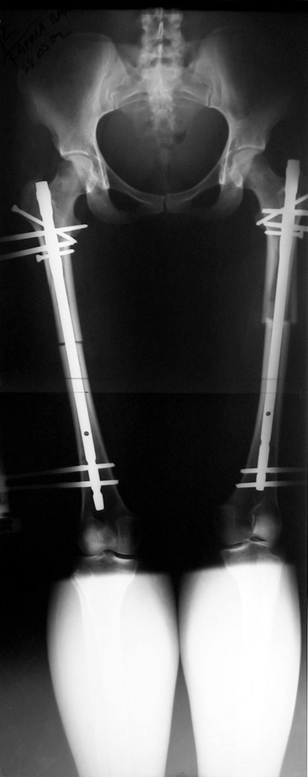

Installment of the intramedullary nail and osteotomy:

The patient lies is supine position at a traction table and legs are crossed with the uninvolved leg at the bottom. The medullary cavity is penetrated through piriform fossa using the standard method, and medulla is reamed 1.5 mm thicker than the nail to be used, over a guidewire. Proximal femur is reamed more, because the intramedullary nail is thicker proximally. The osteotomy site is planned at the X-Rays. It is important that at least 8 cm. of nail remains distal to the osteotomy site after the completion of the lengthening procedure. Percutaneous corticotomy is performed. The guide wire is advanced distally in order to measure the length of the nail. An intramedullary nail of apropriate length is placed. In the end, the nail is interlocked proximally, a suction drain is placed and the fist step of the operation is completed.

2. Step:

The application of the external fixator: Three Schanz screws are placed distally and three screws are placed proximally. At least 1 mm of distance shall remain between the screws and the nail.

In selected cases, we prefer to use a combination of a unilateral dynamic axial fixator and an interlocked intramedullary nail, in order to protect the length and alignment after the completion of the lengthening procedure. As a prerequisite for this technique, the narowest diameter of the medullary cavity shall be wider than 7 mm and the length of the nail segment distal to the osteotomy site shall be at least 8 cm. after the completion of the lengthening procedure.The intramedullary nail neutralizes shear and bending forces on femur during lengthening, shortens external fixation time, and protects newly formed bone against fractures. In our series, subtrochanteric osteotomy was performed in one case. No varus angulation occured despite the intramedullary nail.